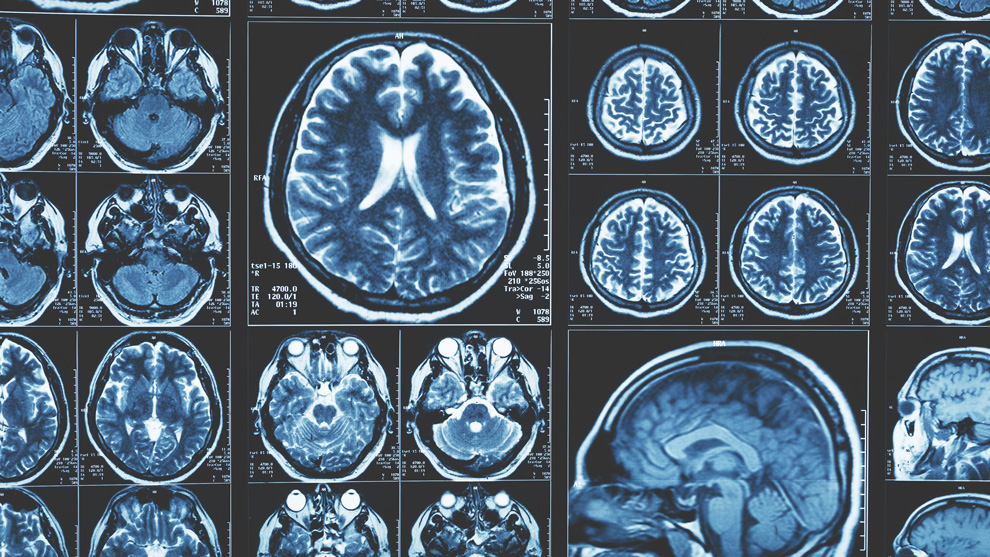

The new approach requires just one of these – a magnetic resonance imaging (MRI) brain scan taken on a standard 1.5 Tesla machine, which is commonly found in most hospitals.

The researchers adapted an algorithm developed for use in classifying cancer tumours, and applied it to the brain. They divided the brain into 115 regions and allocated 660 different features, such as size, shape and texture, to assess each region. They then trained the algorithm to identify where changes to these features could accurately predict the existence of Alzheimer’s disease.

Using data from the Alzheimer’s Disease Neuroimaging Initiative, the team tested their approach on brain scans from over 400 patients with early and later stage Alzheimer’s, healthy controls and patients with other neurological conditions, including frontotemporal dementia and Parkinson’s disease. They also tested it with data from over 80 patients undergoing diagnostic tests for Alzheimer’s at Imperial College Healthcare NHS Trust.